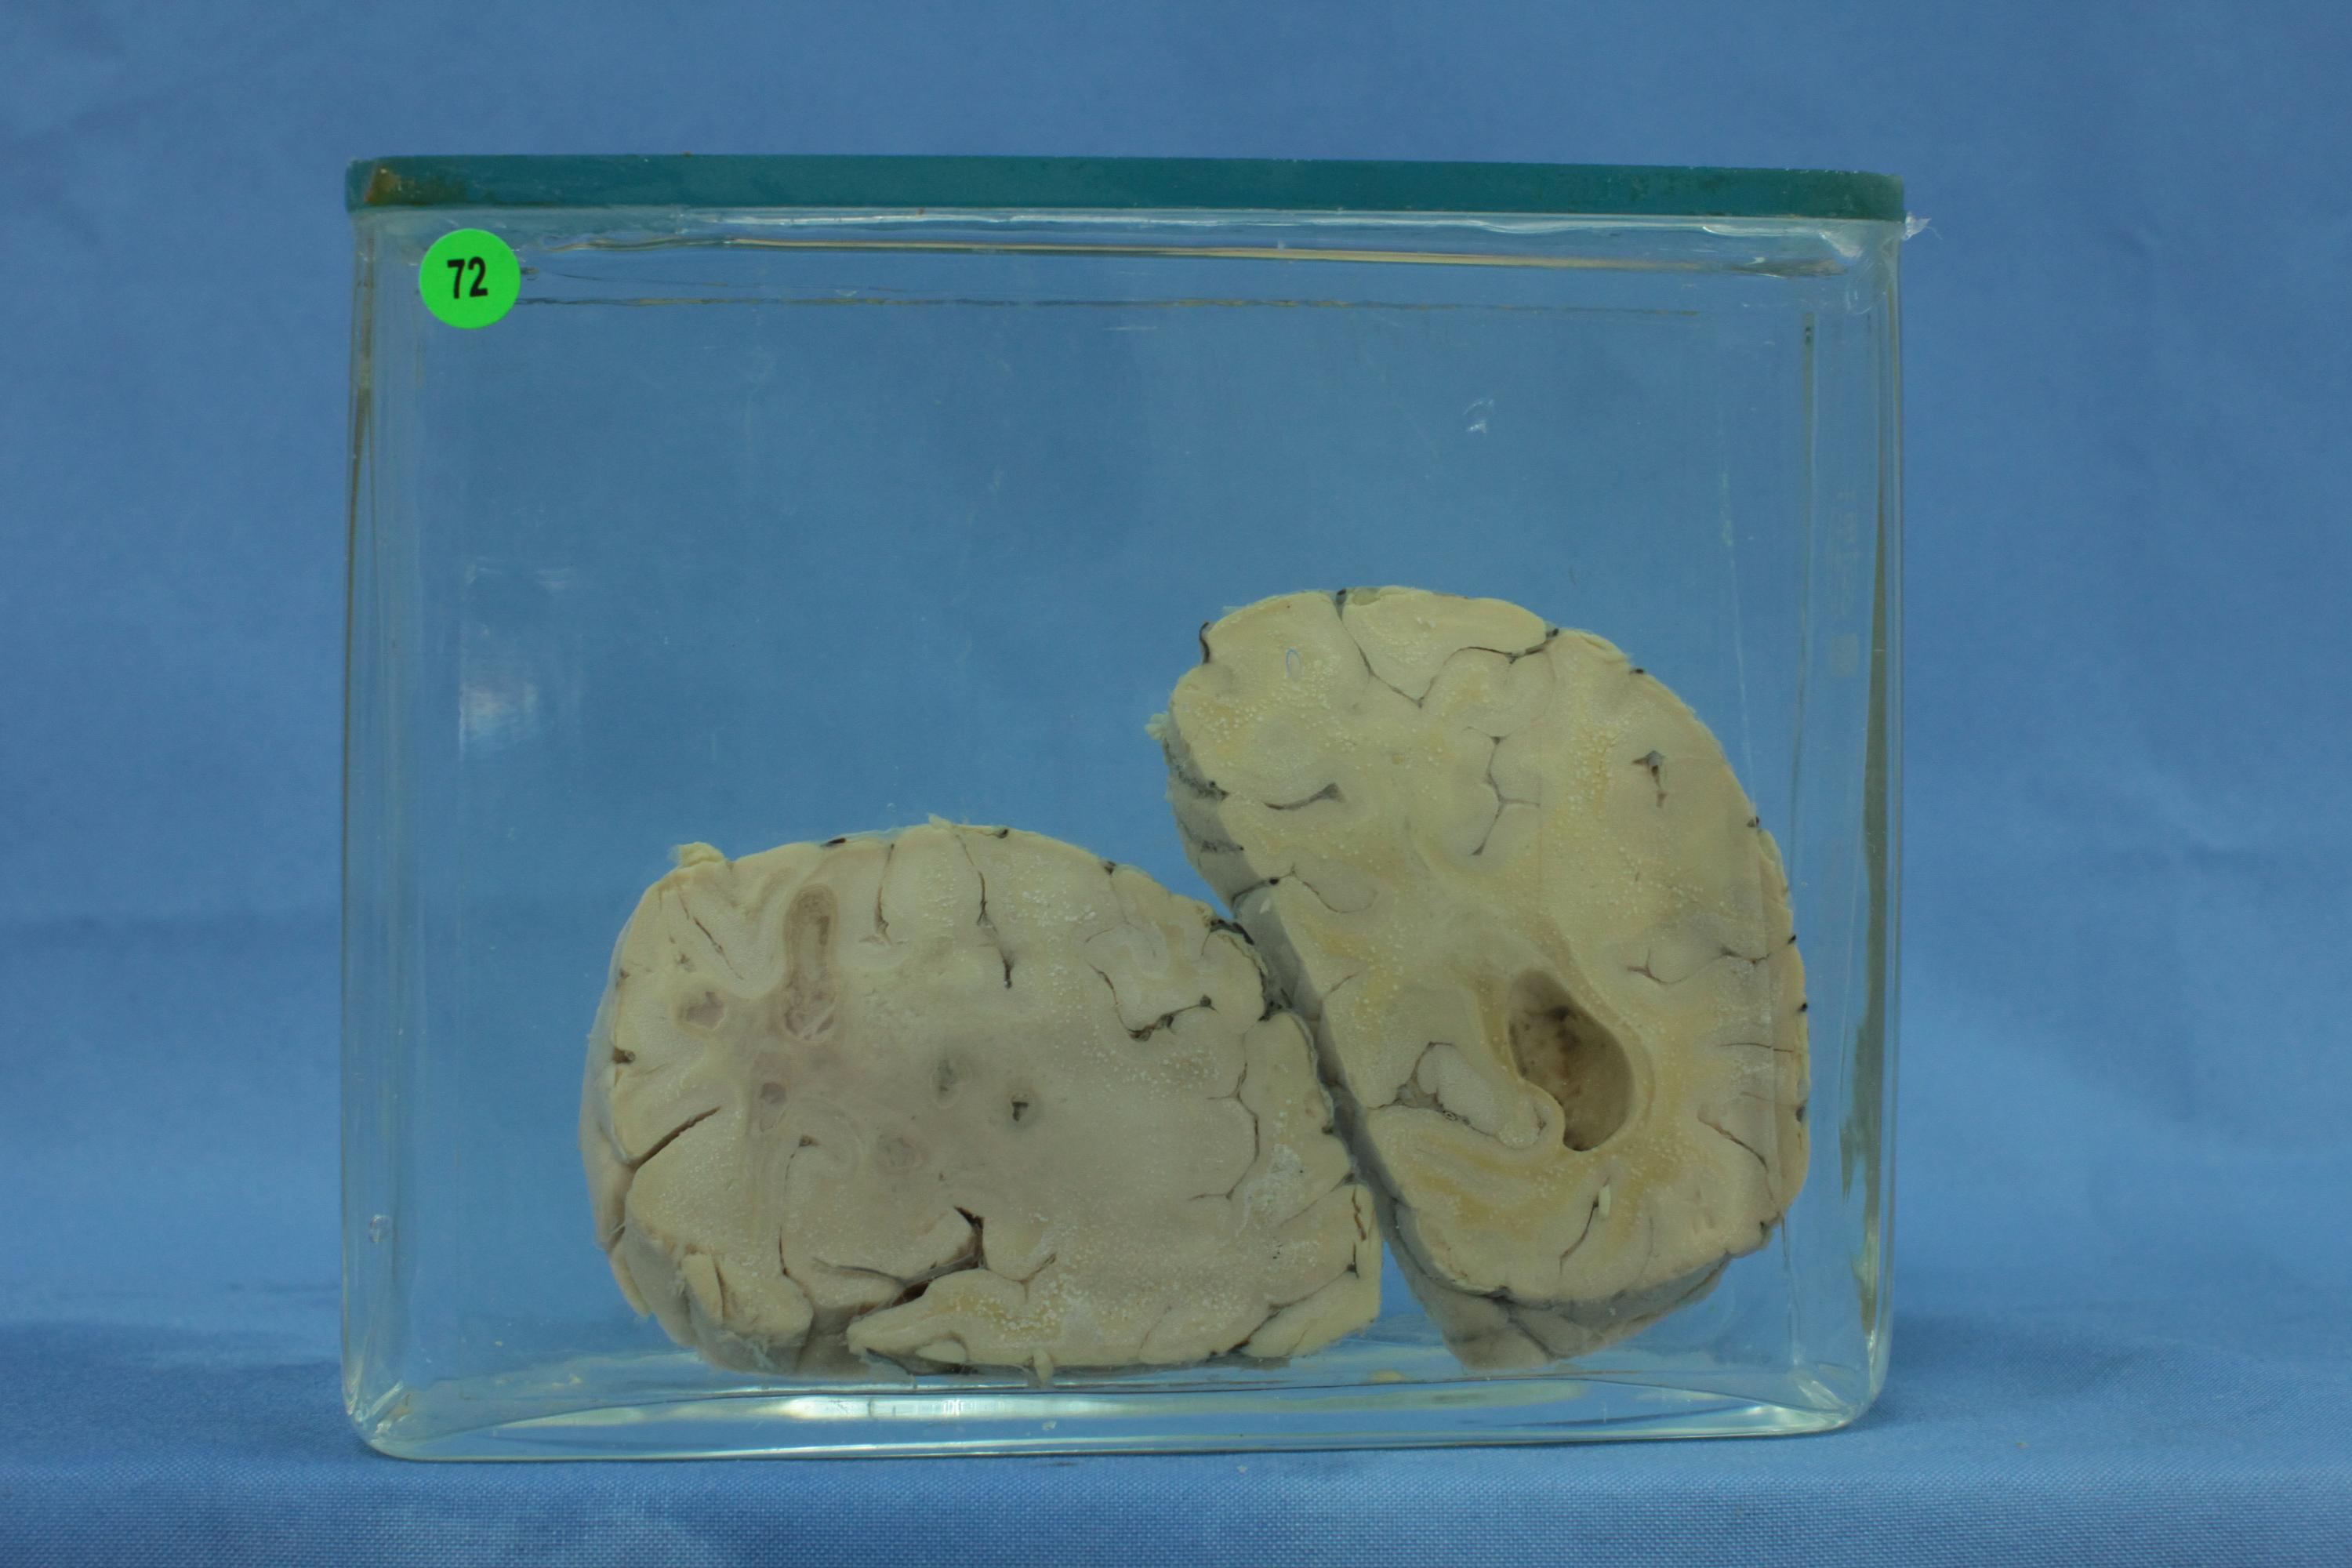

寄生虫病111-72. 脑肺吸虫病

患者男性,23岁,肺吸虫病。大脑冠状切面,脑实质内留有虫体穿行及暂时居留而形成互相沟通新旧不一的隧道及脓肿。